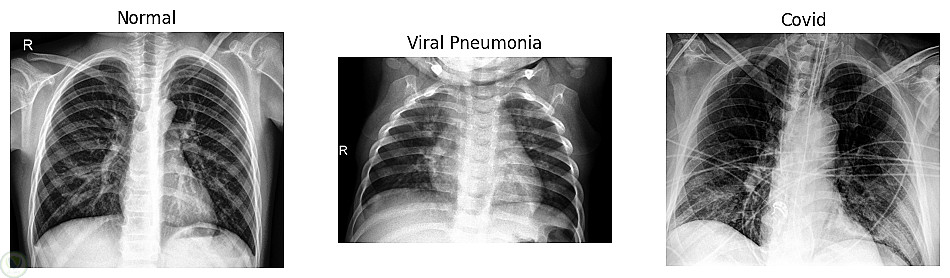

في هذا المشروع قمت بتطوير نموذج تعلم عميق قادر على تصنيف صور COVID-19 بدقة عالية باستخدام معماريتين أساسيتين:

يعتمد النظام على تحليل صور الأشعة وتعلم الأنماط البصرية المرتبطة بالإصابة بفيروس كورونا، وذلك باستخدام مكتبات TensorFlow و Keras في بيئة Python.

تجهيز بيانات الصور ومعالجتها (Preprocessing)

تصميم وبناء نموذج MLP للتصنيف

تصميم نموذج CNN لاستخراج الميزات بدقة أعلى

مقارنة أداء النموذجين باستخدام دقة التصنيف ومصفوفة الارتباك